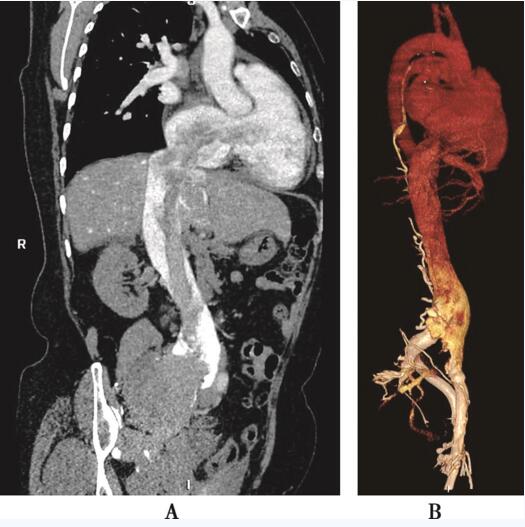

盆腔彩色多普勒超声:盆腔(右侧区为主)可见巨大不规则实性混合回声包块,大小约14.8cm×6.1cm×18cm,边界欠清,内部回声不均匀,其右上方与下腔静脉及髂静脉内肿物分界不清。双髂股静脉彩色多普勒超声:下腔静脉全程内可见不规则条索样低回声肿物。CT:盆腔内可见一低密度分叶状团块,此团块通过右侧髂内静脉及髂总静脉进入下腔静脉,最后入右心房(图85-3)。

图85-3 CT提示下腔静脉及右心房内占位性病变 A:矢状位重建示盆腔内低密度团块通过下腔静脉延伸到右心房内; B:下腔静脉CT静脉造影示下腔静脉内占位性病变